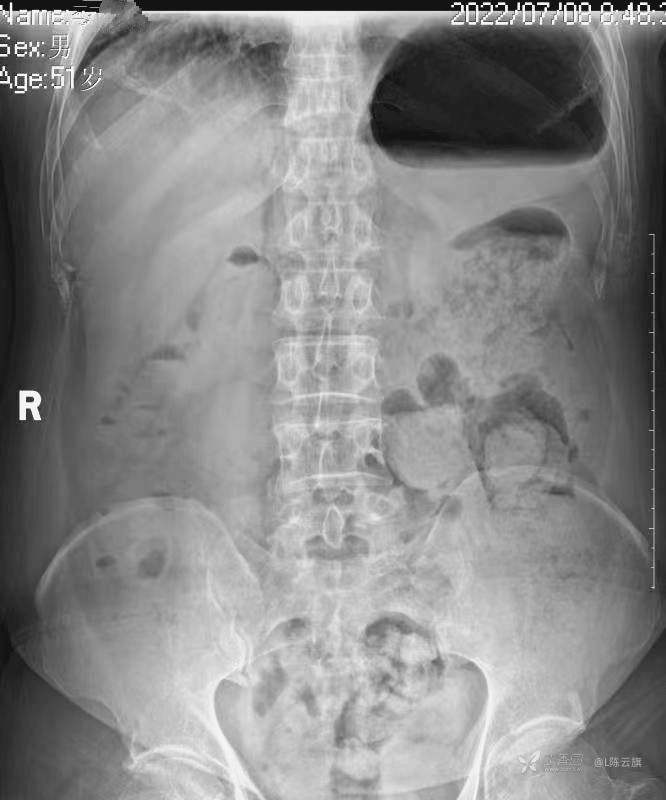

2、第一张腹部立位片是个腹部病变的典型平片表现,你能明确诊断吗?

3、根据系列复查胸、腹部平片的不同表现,你能否总结出什么征象和经验呢?